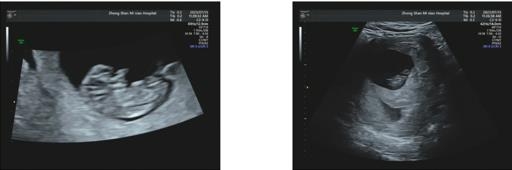

成功获卵冷冻6枚囊胚,5月顺利移植,一次验得好孕,现在已经顺利三超毕业啦!